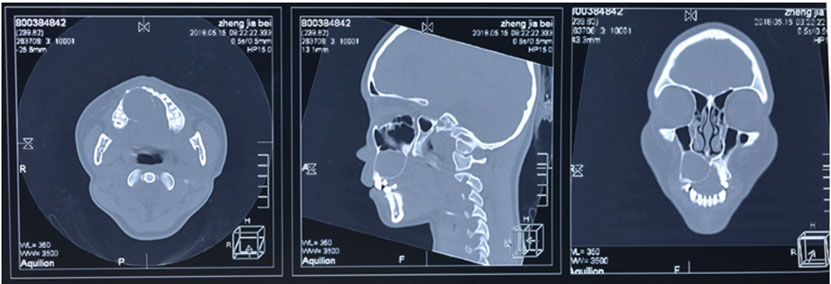

Blood examination showed elevated C-reactive protein levels. Computed tomography (CT) revealed a mass in the right cerebellum, obstructing the fourth ventricle and causing acute hydrocephalus (Figure 2A). On the bone window, the occipital bone had osteolytic change beneath the skin lesion (Figure 2C). The lesion had an enhanced cystic appearance on the contrast CT (Figure 2B). We suspected of brain abscess of the cerebellum caused by soft tissue infection. Emergency cyst drainage was performed. The aspirated fluid was serous and the microbiological examination was negative. Gadolinium-enhanced magnetic resonance imaging (MRI) was performed after the operation. Magnetic resonance imaging results showed shrinkage of the cyst, and the decreased mass effect improved the occlusive hydrocephalus (Figure 2D). There were no findings that indicated brain abscess on diffusion-weighted image (DWI) (Figure 2E). We performed an 18F-fluorodeoxyglucose positron emission tomography (FDG-PET) CT scan to examine potential differential diagnoses, such as metastatic brain tumor or primary brain tumor. There was no uptake of FDG in the body or the cyst, suggesting an absence of primary cancer of the body. Instead, there was uptake on the occipital, nuchal skin (Figure 2F), and on the right side of the 12th thoracic vertebrae. Based on these findings, we suspected a skin tumor, and consulted dermatology. A punch biopsy of the occipital scalp was performed. Histologically, proliferation of tumor cells similar to basal cells is typically observed from the epidermis to the dermis. In the basal layer of the tumor, there was a gap between the palisading arrangement and surrounding connective tissue, mixed with melanocytes. Diverse and solid, lace-like proliferative images, and keratinized vesicles were also observed (Figure 3A and Figure 3B). Based on the histological findings, the diagnosis was BCC.

Figure 2: (A) CT demonstrated a cystic hypodense lesion in the posterior fossa. (B) Contrast enhanced CT revealed an enhanced cyst (55 × 30 × 40 mm). (C) Bone window showed osteolytic destruction on the occipital bone. (D) Postoperative contrast-enhanced MRI demonstrated a smaller enhanced cyst. (E) DWI showed an absence of high intensity in the lesion. (F) FDG uptake occurred in the occipital scalp erosion (Coronal).